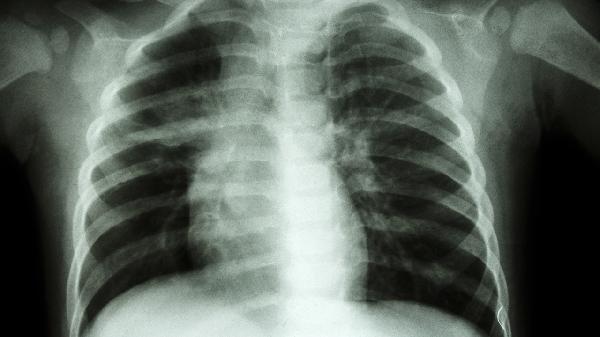

使用矽肺宁片期间应避免接触粉尘环境,配合氧疗和呼吸训练可改善肺功能。建议定期复查胸部影像学,若出现恶心、皮疹等不良反应需及时就诊。日常需保持居室空气流通,适当进行有氧运动增强呼吸肌力,饮食宜选择高蛋白、高维生素食物辅助肺部修复。